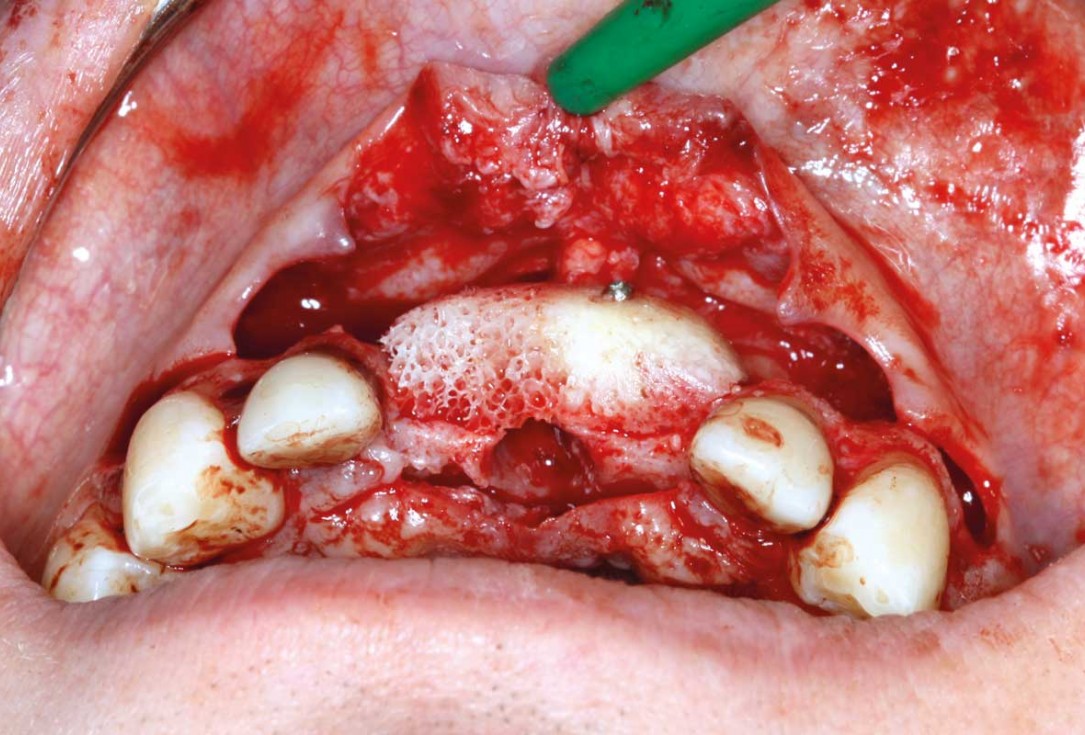

05/26 - Positioning of maxgraft® bonebuilder

Ridge augmentation in the maxilla with maxgraft® bonebuilder in the aesthetic zone - Dr. M. Kristensen